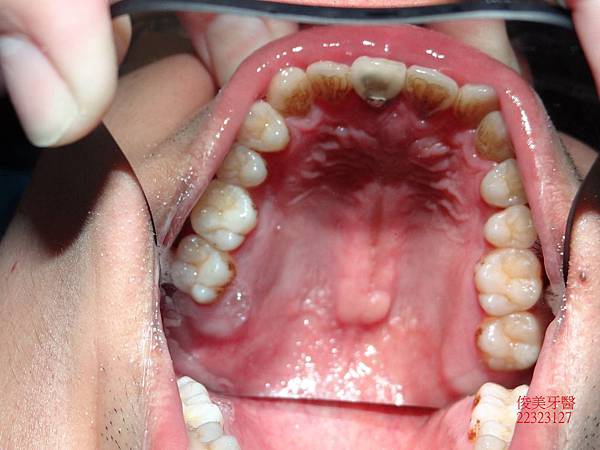

上顎牙弓形狀

下顎牙弓形狀